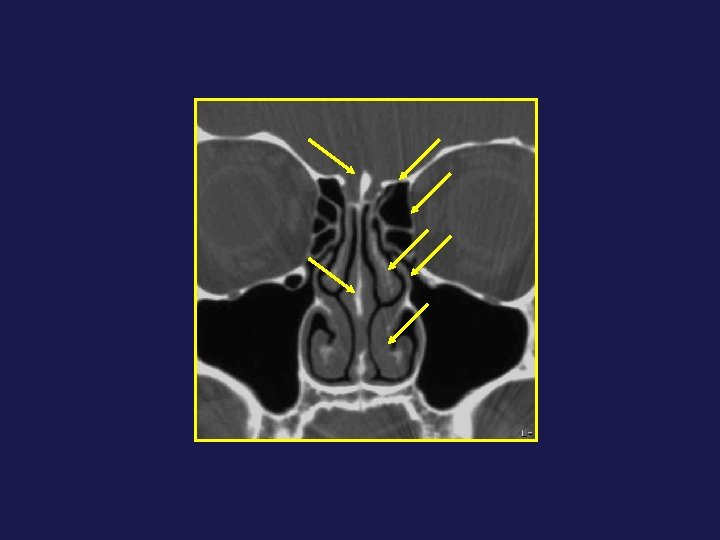

INFUNDIBULUM Cloison intersinusienne Bec nasofrontal ↓ OSTIUM

Le drainage se fait à travers un complexe anatomique : Tractus nasofrontal 2. Infundibulum

Le drainage se fait à travers un complexe anatomique : Tractus nasofrontal 2. Infundibulum frontal 3. Ostium frontal 8. Récessus frontal 1 2 4 7 3 8 5 9

Le drainage se fait à travers un complexe anatomique : Tractus nasofrontal 2. Infundibulum frontal 3. Ostium frontal 8. Récessus frontal 1 2 4 7 3 8 5 9 4 - Bec nasofrontal 5 - Agger Nasi 7 - Bulle ethmoïdale 9 - Racine cloisonnante du CM